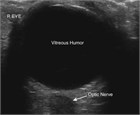

Patients may present with visual complaints of acute monocular floaters or flashes of light. The most common cause is a posterior vitreous detachment, but a retinal detachment or tear, cerebrovascular causes, and vitreous hemorrhage also must be considered. A retinal detachment requires urgent ophthalmology referral whereas a posterior vitreous detachment can be seen in follow-up. The history along with visual acuity, detailed ophthalmologic and fundoscopic exam, and bedside ultrasound can aid in the diagnosis.

ocular ultrasound